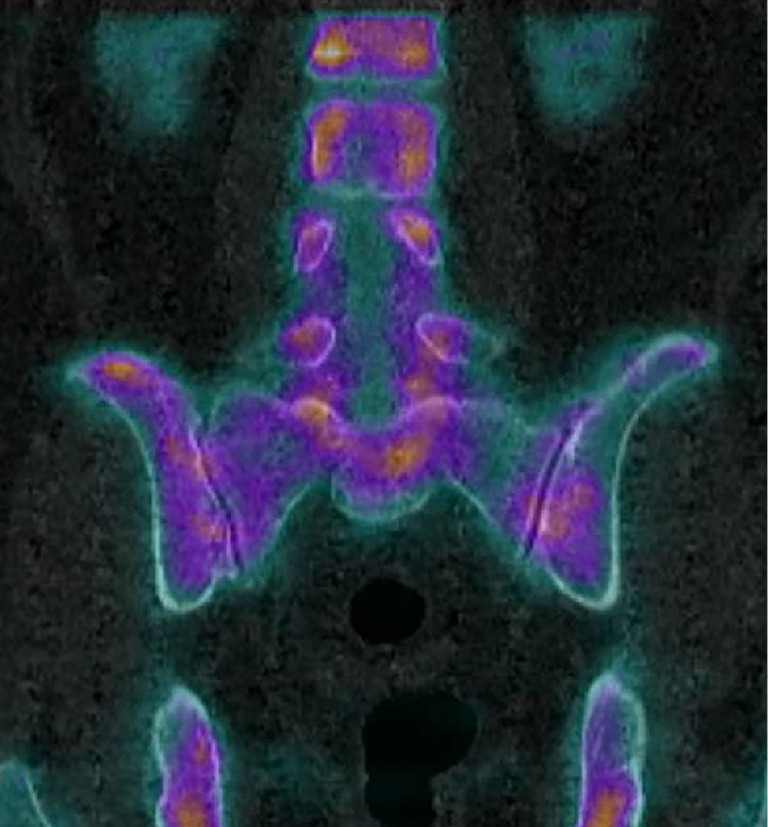

Case description: We present the case of a 76-year-old woman with a 1-year history of progressive left-sided low back pain that progressed along an S1 radicular distribution and became debilitating, interfering with their activities of daily living. Specifically, the pain radiated along the left buttocks, down the posterior aspect of the leg, and into the heel. SPECT/CT demonstrated non-specific, symmetric radiotracer uptake within the bilateral SI joints. She had a positive response to two SI joint injections. The patient was ultimately treated with a SI joint fusion. This case raises questions regarding the sensitivity and specificity of SPECT/CT for SI joint pain. A minimally invasive surgery (MIS) lateral SI joint fusion using navigated and fenestrated screws can provide significant pain relief.